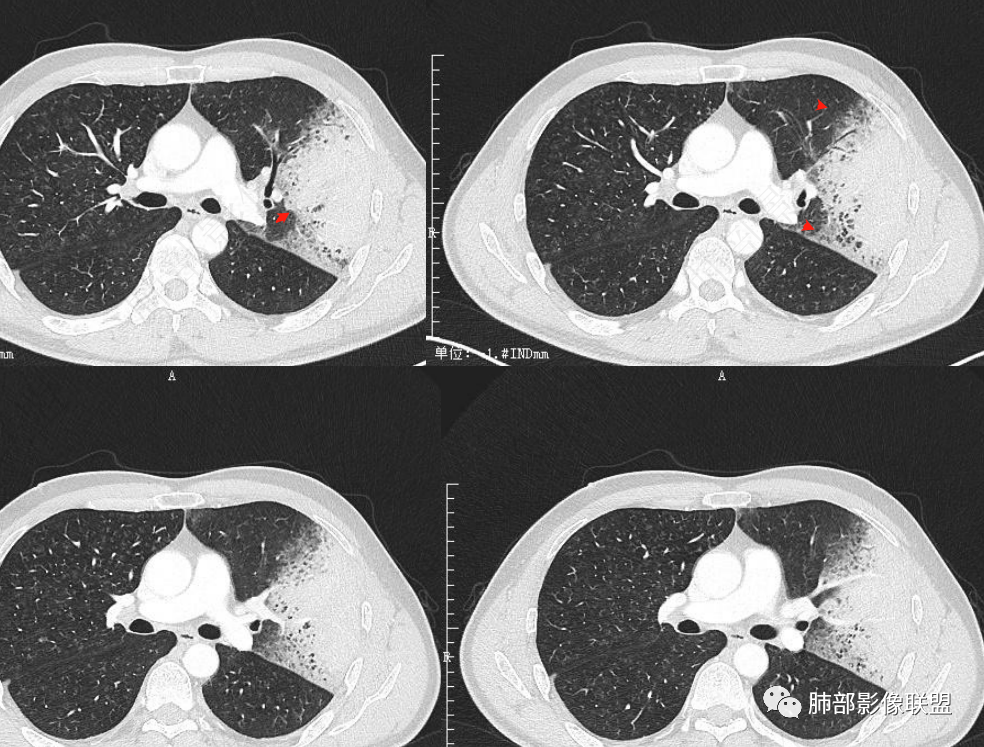

2.左肺上叶大片状混合密度影,未见空洞,实变影主要位于胸膜下,长轴与胸膜平行,实变区内部密度不均、其内可见多发小斑片状低密度影,磨玻璃影多位居肺门一侧,可见网格,磨玻璃影边界多可分辨,重力分布趋势。病灶区支气管显示较为通畅,进入外围实变区渐至消隐。病灶轻度不均匀低强化,病灶区肺动脉显示较良好,未见破坏。

双肺广泛分布微小磨玻璃密度结节影,腺泡结节样分布,密度大小较为均匀一致。

3. 综上,患者中年男性,长病程,影像上磨玻璃/实性混合密度,边界可分辨,重力分布趋势,支气管通畅,穿行血管较为完好,较为符合典型粘液腺癌或腺癌影像学表现。如影像上进行性进展且出现多肺段多肺叶飘散磨玻璃结节,则更具判断价值!